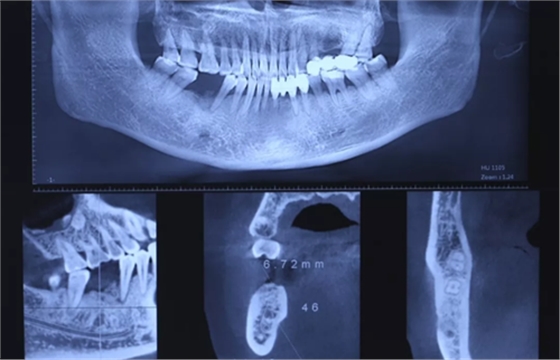

3、术前全景片

46牙烤瓷冠修复,根折伴大范围骨吸收。(摄于2016年8月31日)

10、CBCT检查

CBCT检查测量缺牙区可用骨高度14.40mm,骨宽度6.72mm。

(摄于2017年2月15日)